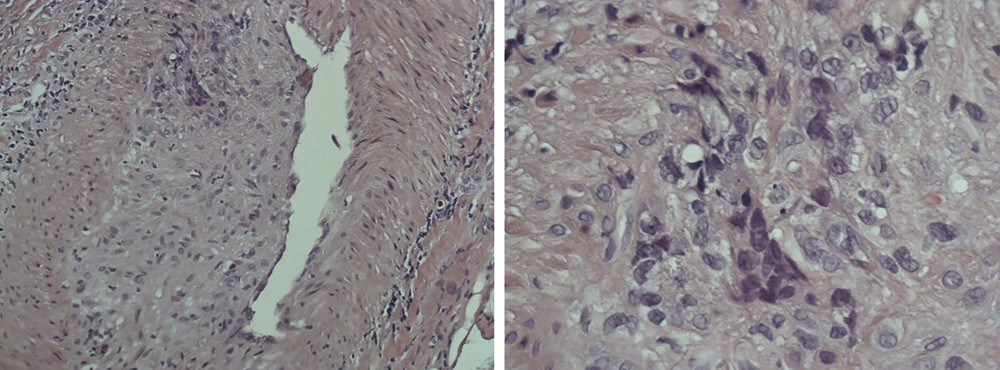

Biopsi av arteria temporalis bekreftet kjempecellearteritt (e-fig). Ved kontroll noen måneder senere følte pasienten seg frisk, og synsfunksjonen var normal. På bildet til høyre kan man se at fluoresceinangiografi av venstre øye viste normal retinal sirkulasjon.